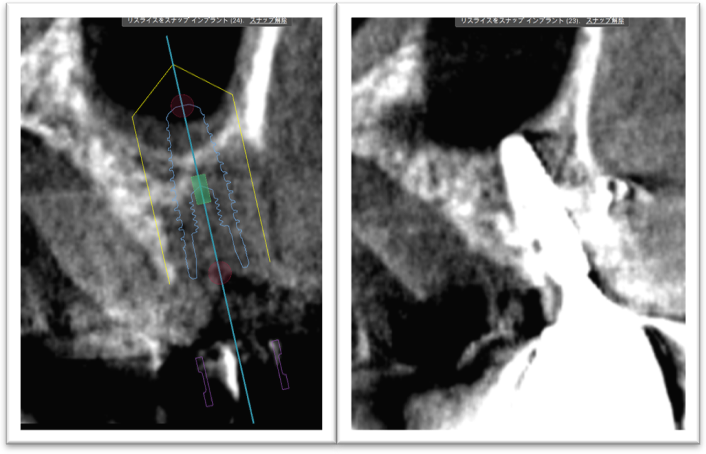

①歯槽頂よりサイナス

リフトを行いました。

②血液成分とカルシウム材料により骨造成をしました。

③ガイデッドサージェリーにてインプラント埋入しました。

④計画通りの埋入が出来ました。